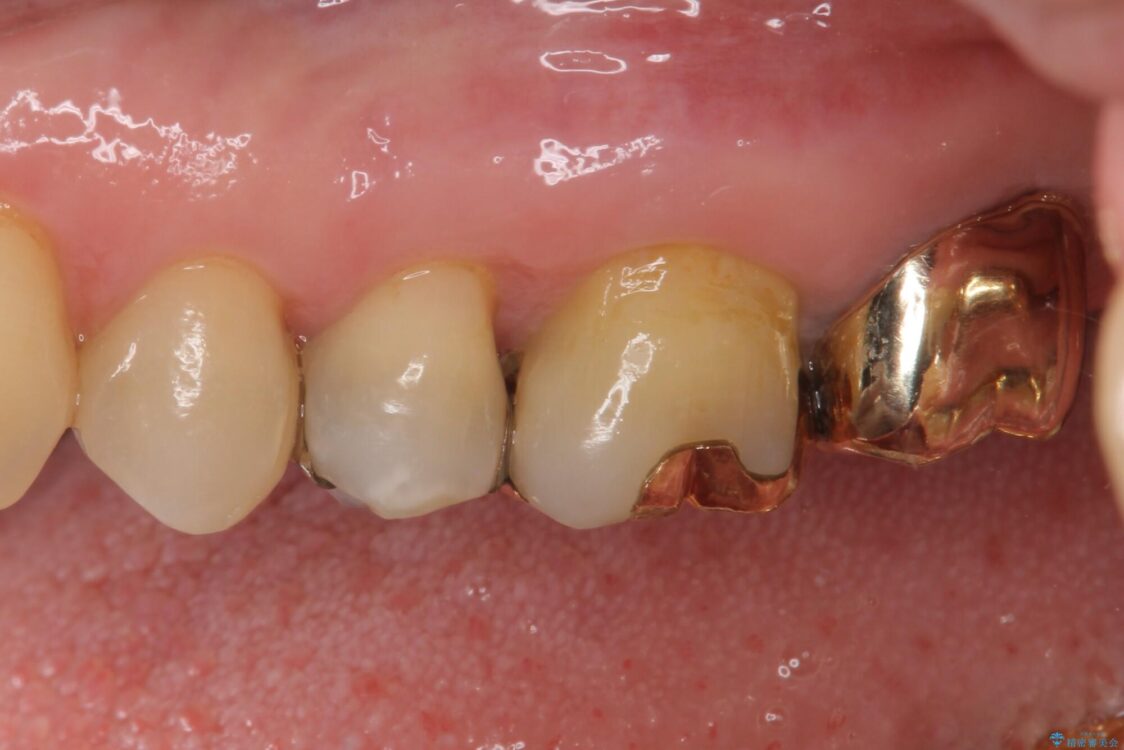

奥歯の銀歯が外れてしまったため、セラミック治療を希望された患者様です。

セラミックインレーによる修復治療を実施しました。

正面から見える場所であったため、セラミックインレーで自然な口元にすることができました。

治療前

• 外れてしまった銀歯 セラミックインレーで自然な仕上がりに 治療前画像